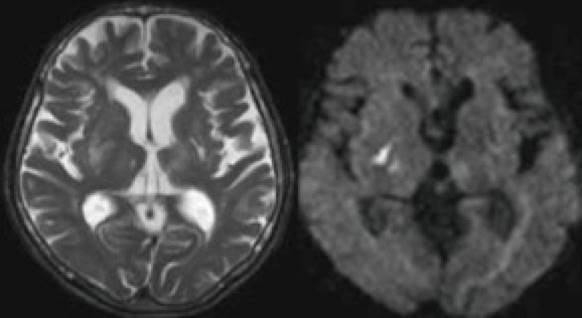

脳梗塞急性期のMRI画像

頭痛・めまい・腰痛や肩こり・手足のしびれの原因検査,顔面や頭部の外傷,脳疾患後の管理や,クモ膜下出血の原因となる脳動脈瘤(脳の動脈にできるコブ)や,初期の脳梗塞の発見など,また,生活習慣病の方の病気の早期発見や予防にも効果的な検査です。